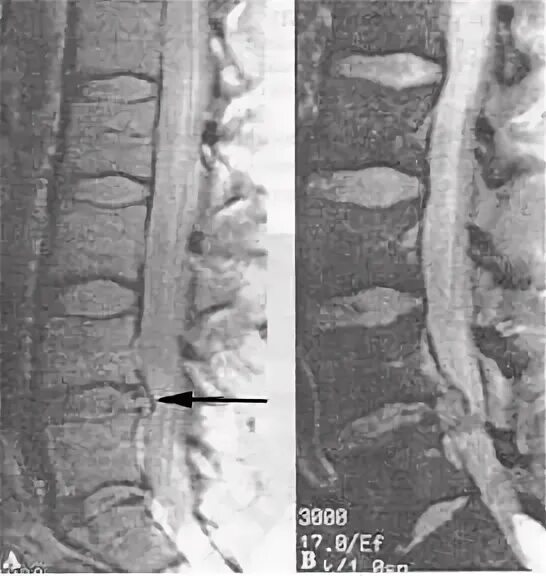

Лфк при грыже l5 s1